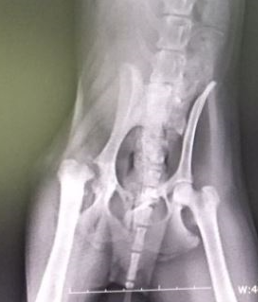

4.1. 정확한 진단과 정기 검진

보호자의 관찰만으로는 한계가 있습니다. 6개월~1년에 한 번씩은 동물병원에 방문하여 수의사의 신체검사(촉진, 보행 평가)와 방사선(X-ray) 촬영을 통해 관절 상태를 주기적으로 확인하는 것이 중요합니다. 이를 통해 질병의 진행 속도를 파악하고 관리 계획을 수정할 수 있어요.